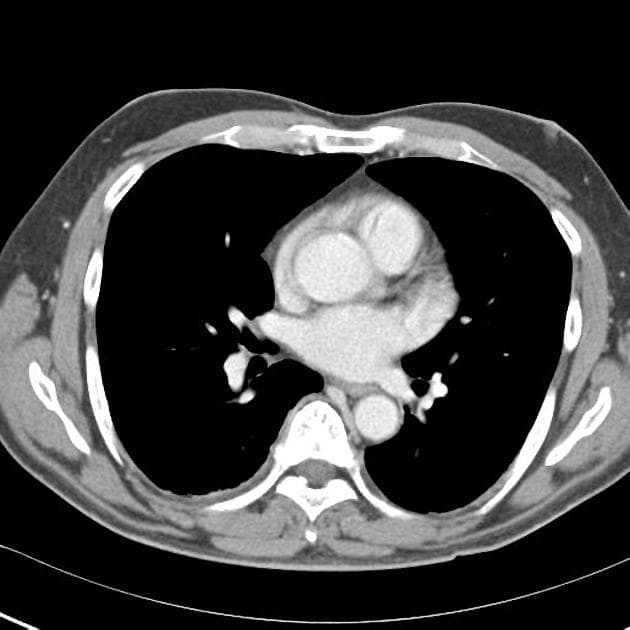

Chụp X-quang bụng và ngực tư thế đứng thấy có khí tự do dưới cơ hoành, gợi ý liềm hơi dưới hoành (pneumoperitoneum).

Các quai ruột vùng hạ vị phải mờ không rõ nét, thành ruột dày, phù nề và không đều. Có ổ dịch vùng chậu chứa khí và chất giống phân (cắt ngang, mặt đứng dọc). Ngoài ra, thấy dịch tự do trong ổ bụng có tỷ trọng hơi tăng nhẹ và hình ảnh liềm hơi dưới hoành (pneumoperitoneum) trên cửa sổ nhu mô phổi.

Dày thành phúc mạc và tăng quang thành phúc mạc, phù hợp với viêm phúc mạc (peritonitis).